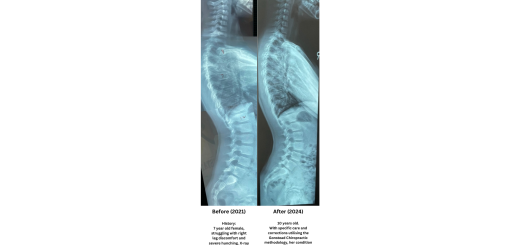

Reduced Hunching and Increment of 2cm Height